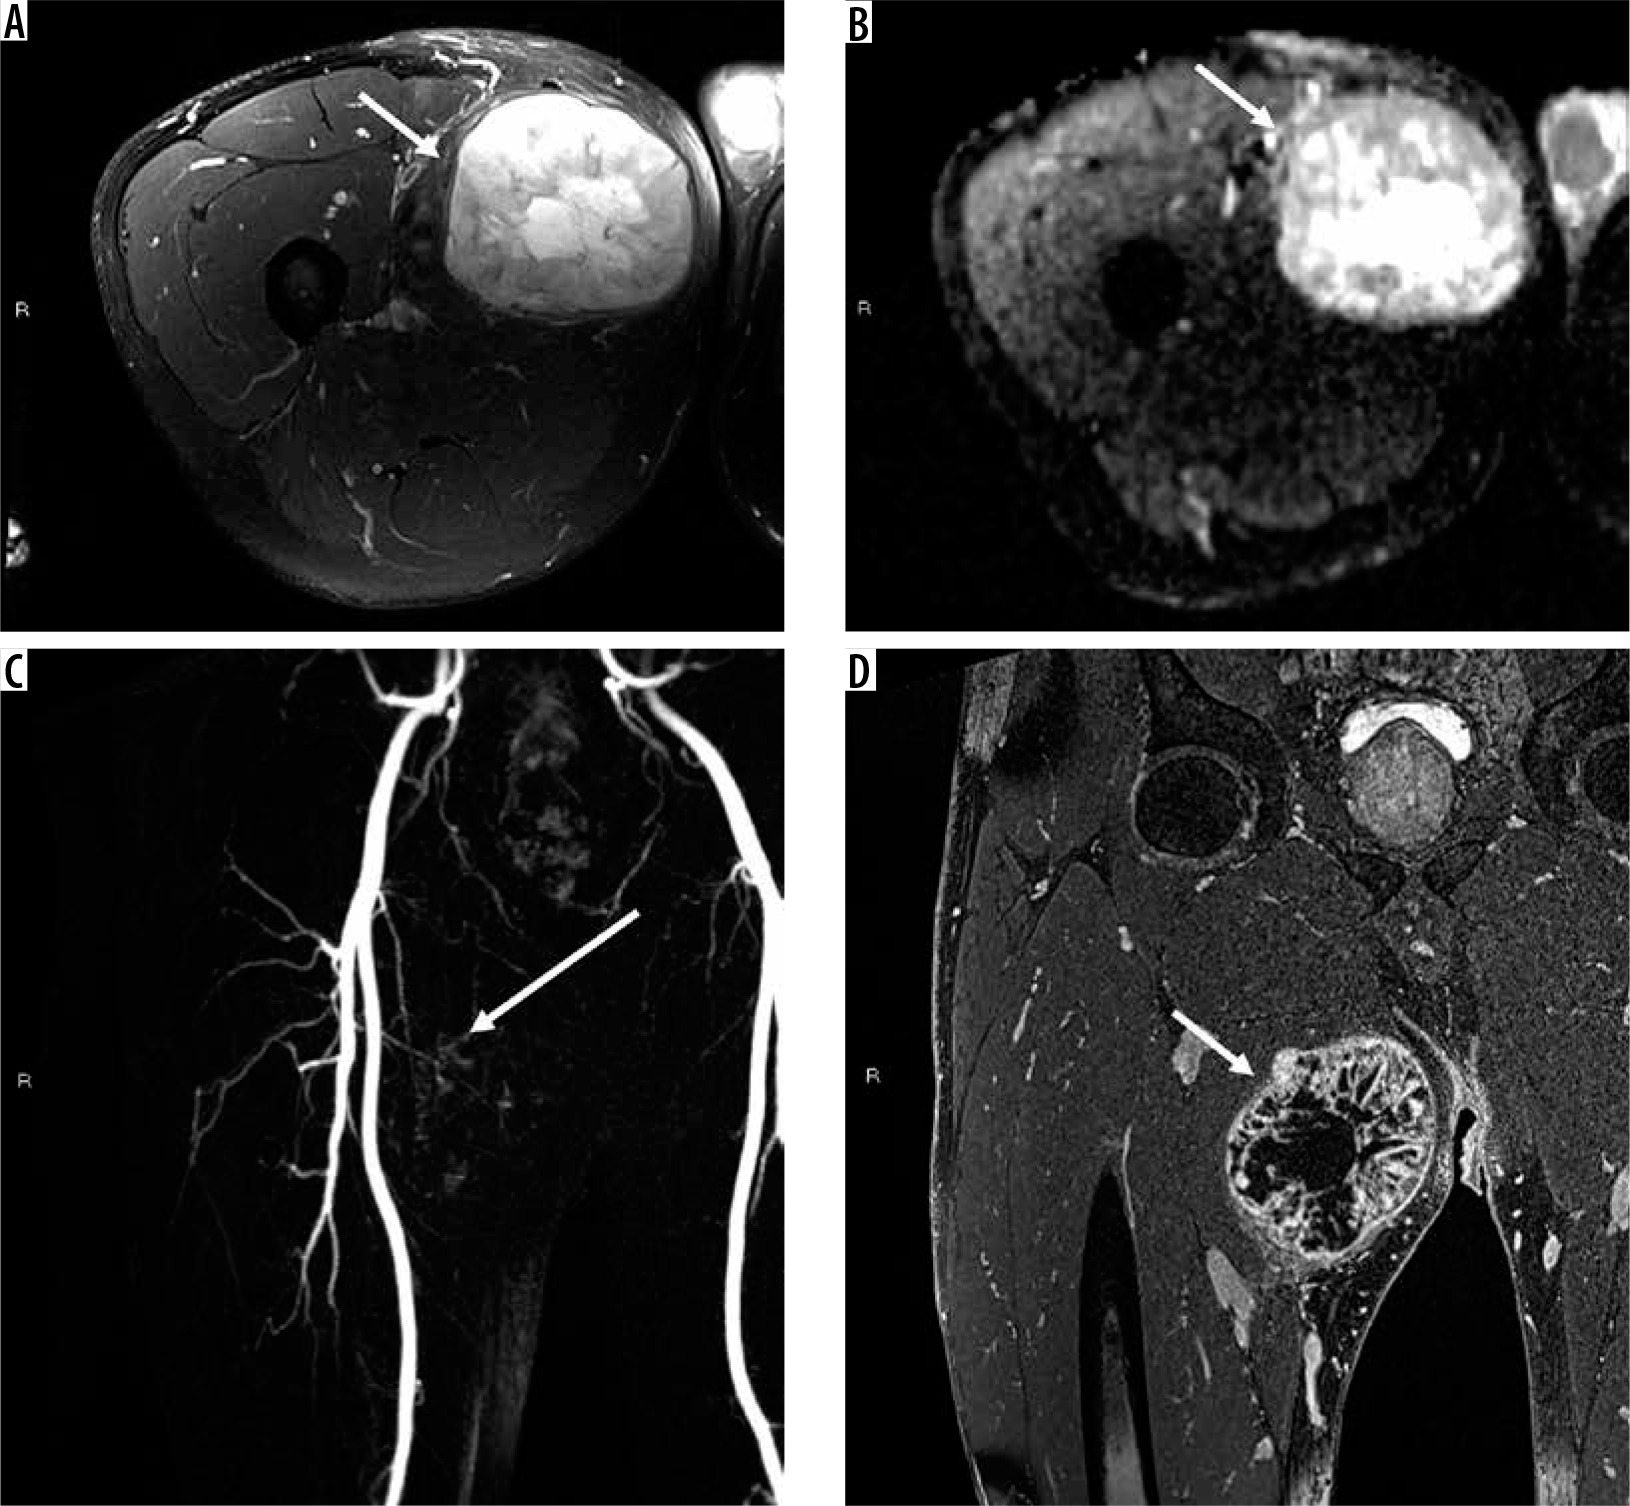

Figure 11

61-year-old woman with grade 3 undifferentiated pleomorphic sarcoma. There is a large 9.6 × 1.5 × 7.4 cm soft tissue mass in the left gluteus maximus muscle (arrows). The mass is hyperintense relative to skeletal muscle T2-weighted fat-suppressed magnetic resonance (MR) image through the left hemipelvis (A) and isointense to skeletal muscle on T1-weighted image (B) with moderately heterogeneous enhancement on post-contrast T1-weighted fat-suppressed image (C). Aggressive MRI features include presence of tumoural necrosis and perilesional oedema/enhancement. There is no extra-compartmental extension